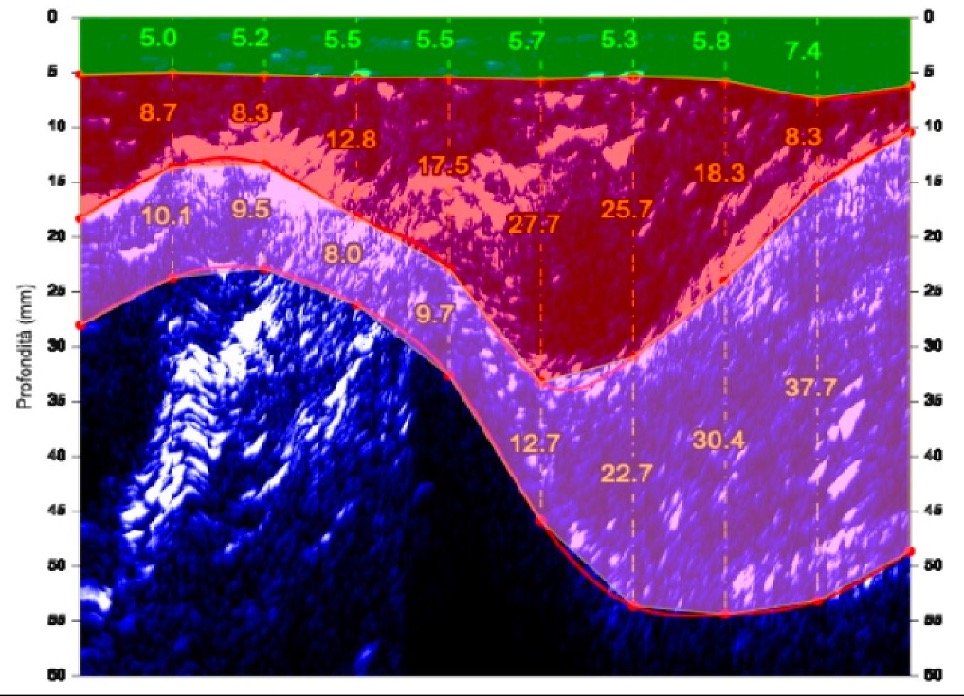

Esempio di stratigrafia su esterno coscia con individuazione degli strati dei tessuti

L’adipometro Hosand BX 2000 che utilizzo, scorrendo sulla zona di misura, crea una mappa dei tessuti sottostanti (stratigrafia), sulla quale è possibile:

• Misurare in millimetri l’adipe, suddividendolo a sua volta in :

• derma (SAT- adipe essenziale)

•  ipoderma (DAT – adipe di accumulo)

• Misurare in millimetri le fasce muscolari

• Valutare i tessuti dal punto di vista qualitativo